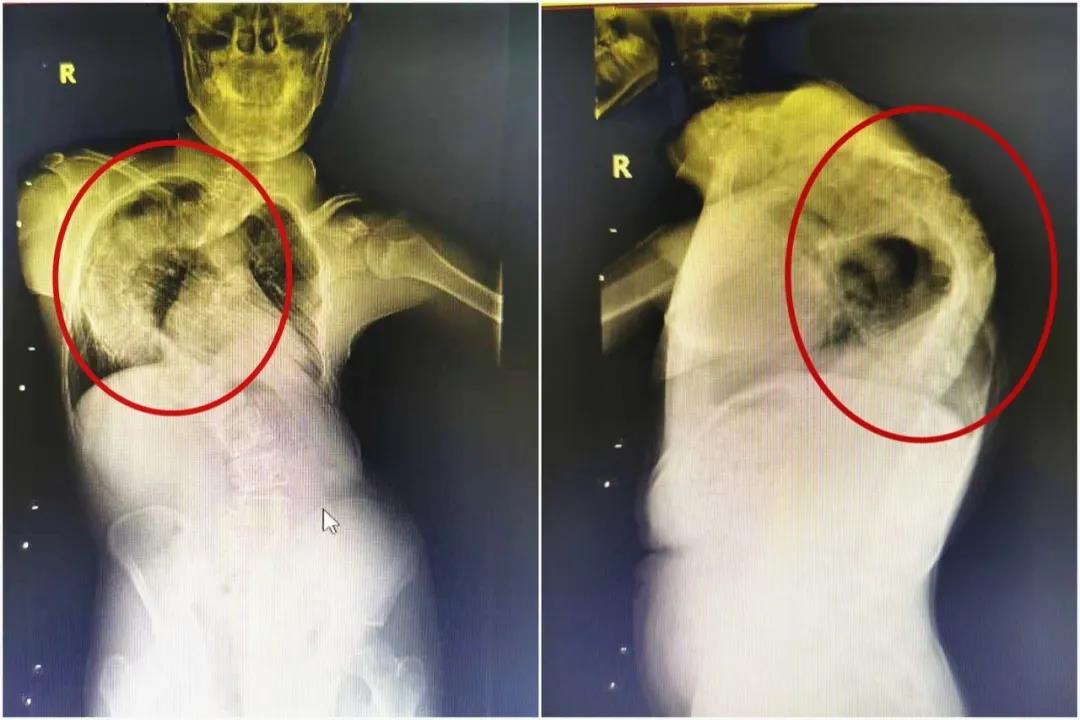

5岁男童脊柱侧弯超100度心肺功能受影响

超过90度我们就叫重度脊柱侧弯,超过100度是极重脊柱侧弯